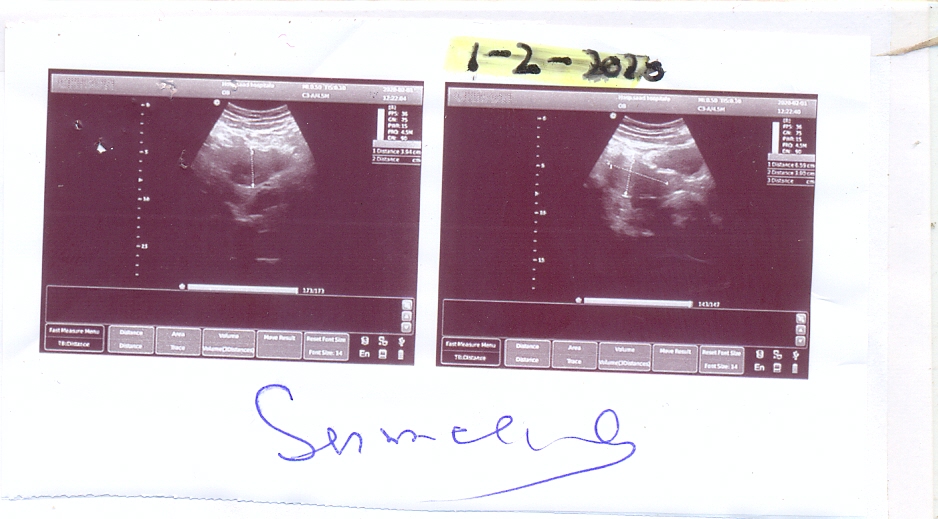

Hello Dr, my wife got 2 miscarriage once, after 1 month of marriage and recently 1 month before, here are Medical report enclosed, kindly tell me what should i have to do, on last docotor vist they advice to take folic acid on night for both

Attach Photo here: